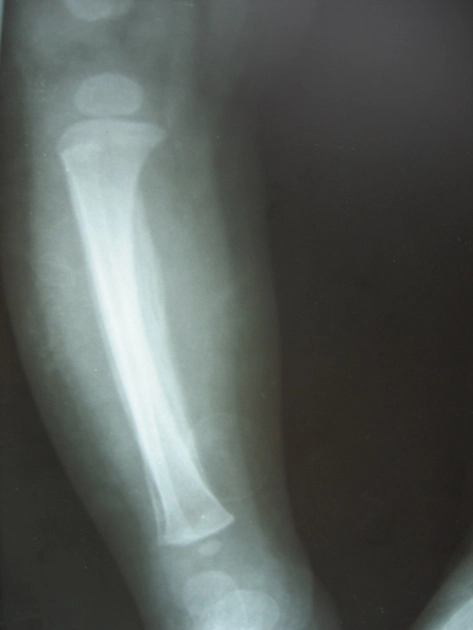

Loạn sản hành xương (Metaphyseal dysplasia)/ Bệnh Pyle

16/03/2026